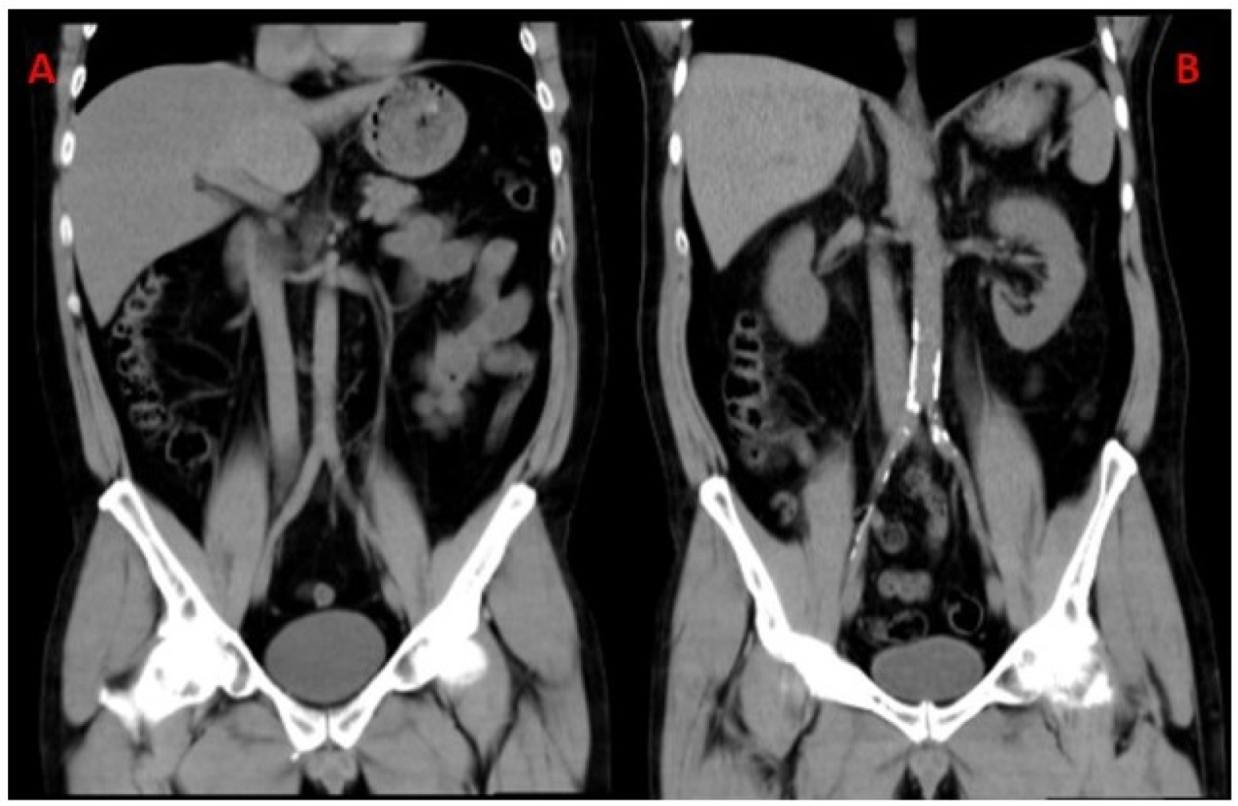

| Abdominal CT | ||||

| Zone 1 (Ag)1 | 0 (0–0) | 0 (0–0) | 0 (0–1.37) | <0.05 |

| Zone 2 (Ag) | 0 (0–51.2) | 0 (0–32.5) | 0 (0–117.45) | |

| Zone 3 (Ag) | 0 (0–142.3) | 0 (0–71.6) | 0 (0–277.85) | |

| Total (Ag) | 0 (0–296.6) | 0 (0–171) | 0 (0–455.07) | |

| Abnormal AACS (%) | 48 (46.61) | 23 (43.4) | 25 (50) | |

| Liver steatosis1 | 20 (19.4) | 6 (11.3) | 14 (28) | <0.05 |